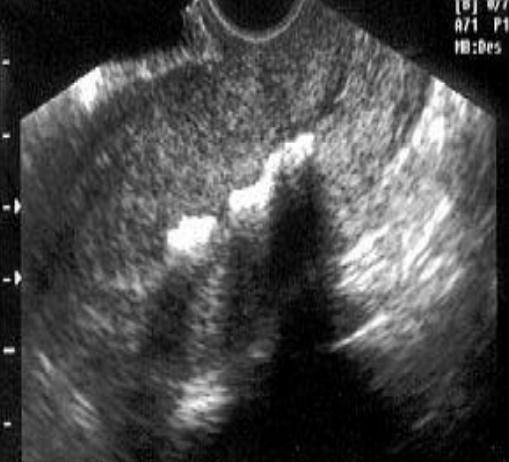

Endometritis (imagen)

Endometritis

Esta mayormente asociado con:

PID.

También puede observarse en pacientes post parto. Sonográficamente observamos la cavidad endometrial prominente e irregular, y podría presentar fluido interno.